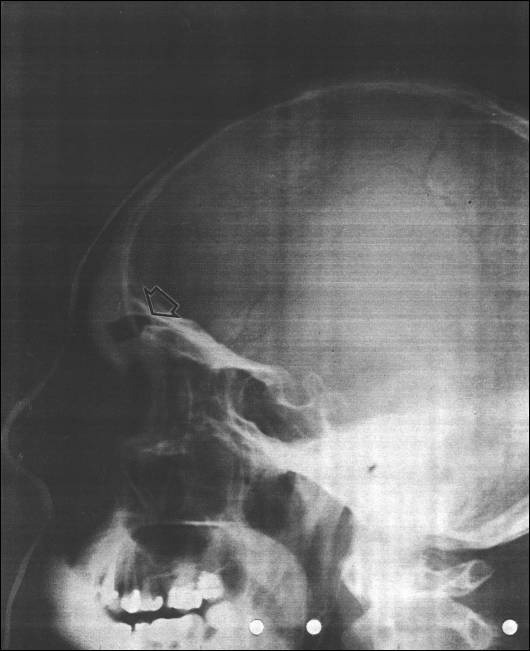

“This X-ray shows three transmitters in the frontal lobes. All of these were implanted on different occasions by the Swedish police. The detainee had been put to sleep unaware, as usual, at the police remand center in Stockholm. A doctor writes in his statement concerning this X-ray: ‘...Later I received your additional skull film which clearly demonstrated some implanted transmitters, one inside the brain and two probably just underneath the brain.’

The upper arrow indicates the object lodged completely within the brain. All these transmitters were inserted through the nostrils and implanted into the frontal lobes in the vicinity of the upper opening of the nasal passage.” — Lennart Lindquist, Evamarie Taylor, and Robert Naeslund, Cybergods, Stockholm: Gruppen, 1996, page 11.